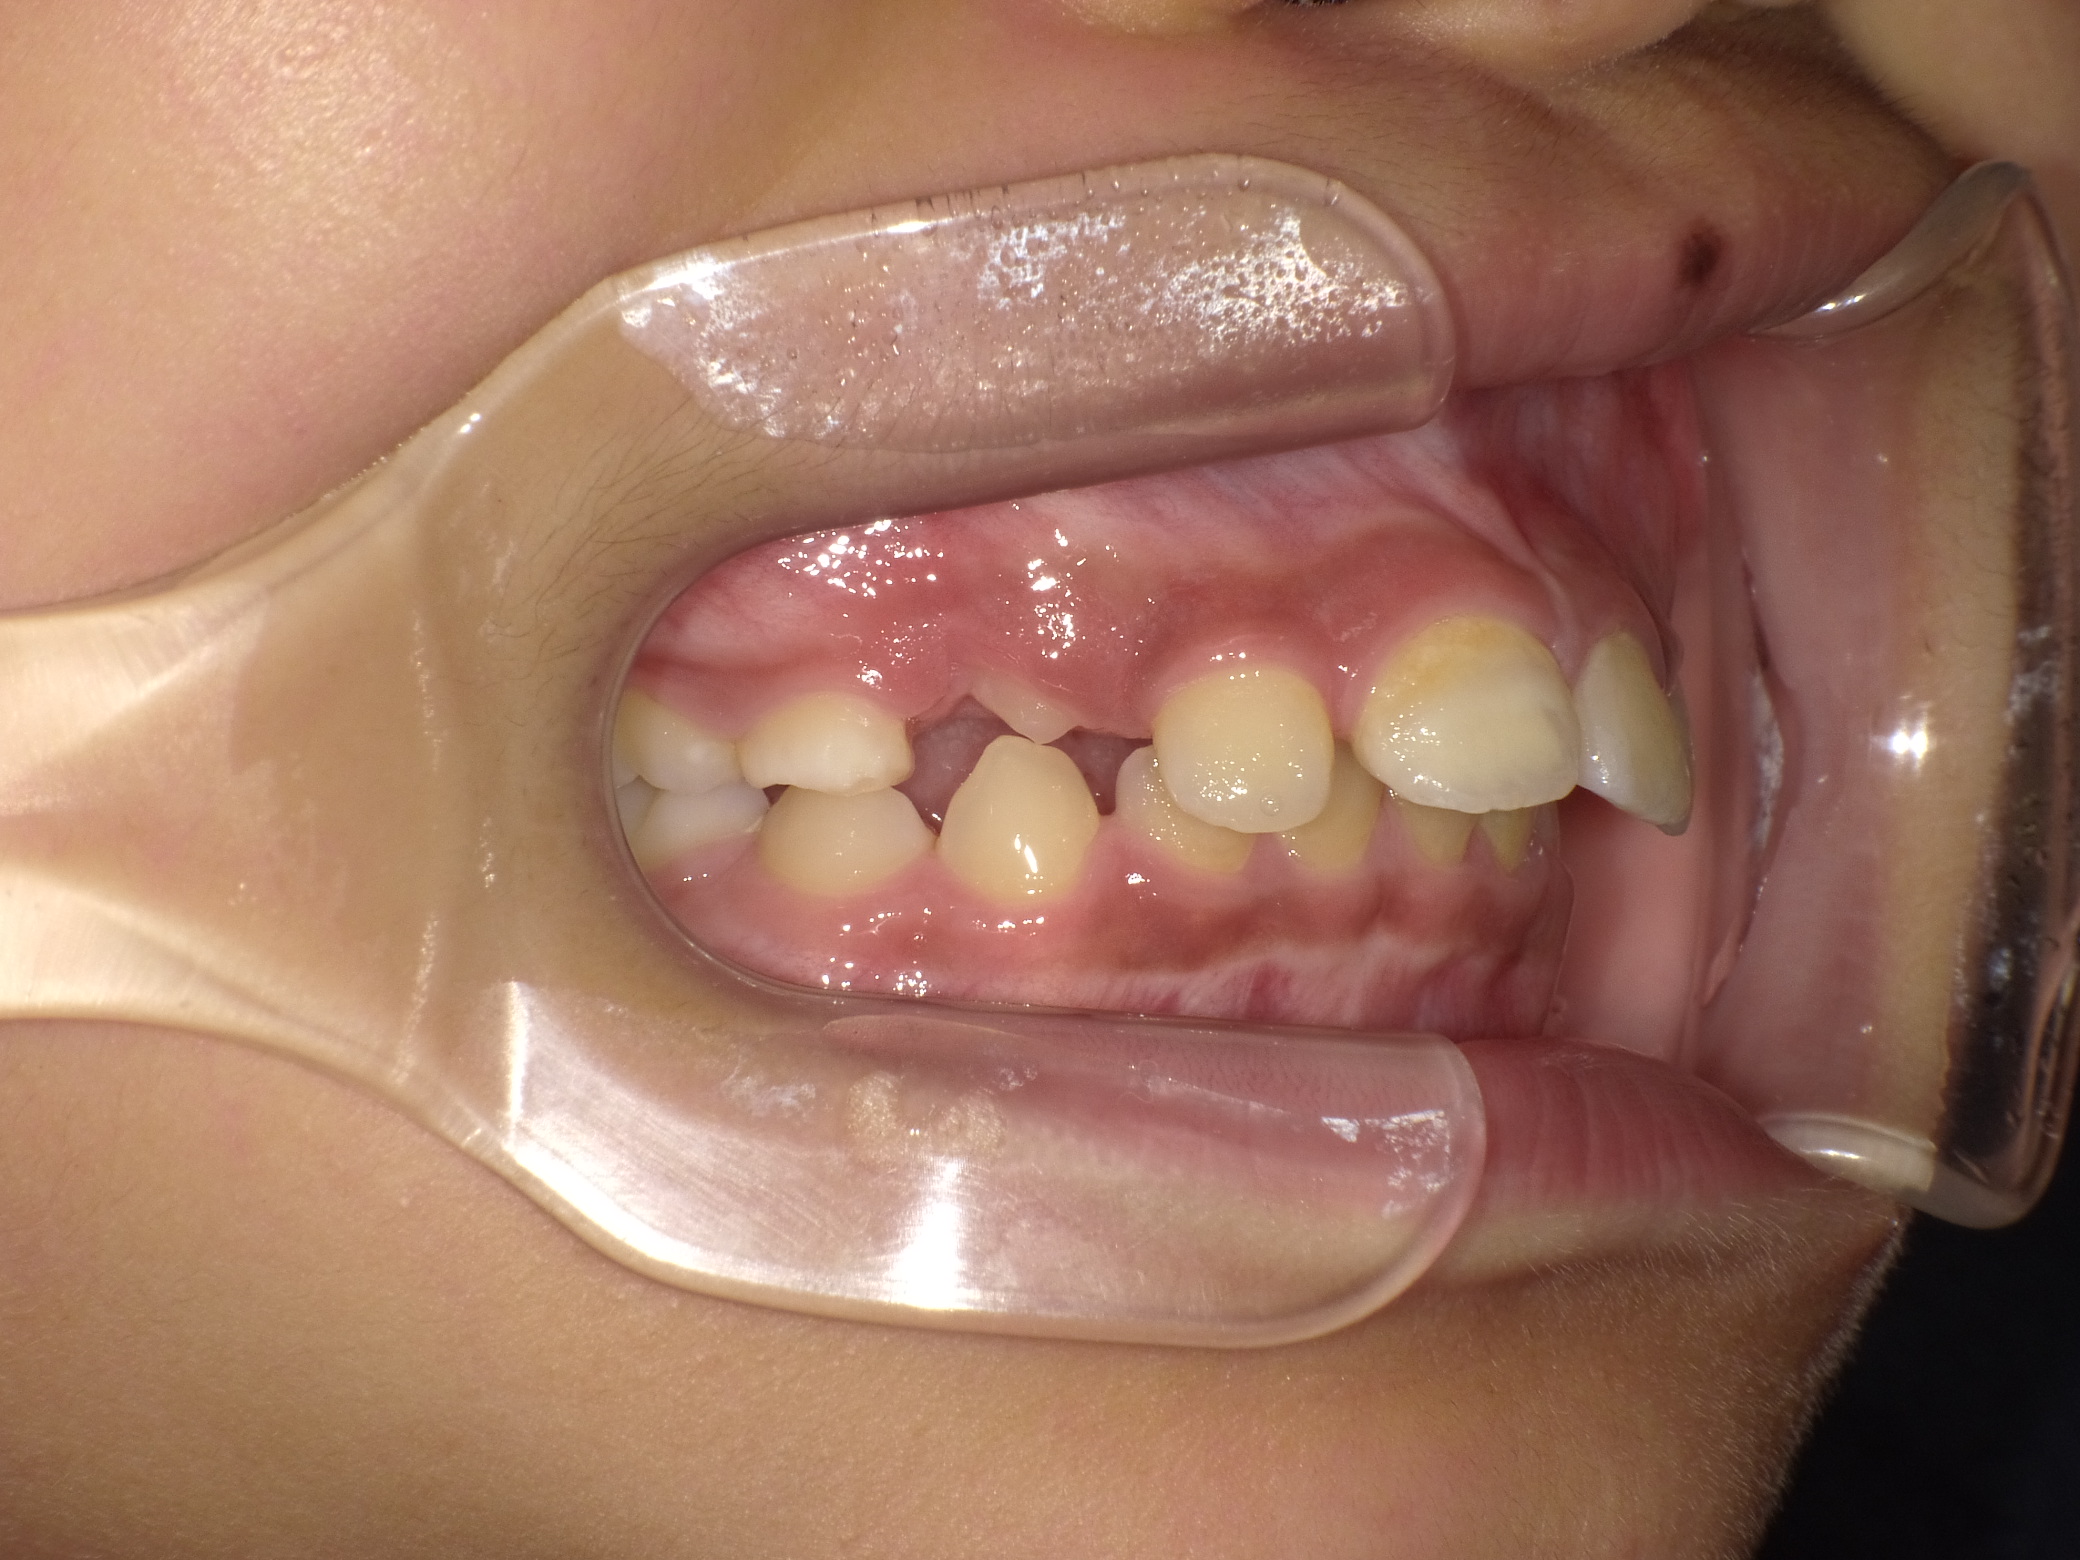

治療前

骨格:上下あごともに前方に出やすい傾向(上下顎前突)

歯並び:前歯の前方への突出(出っ歯傾向)

成長を利用した1期治療にて、マウスピース型装置や矯正装置を用い、歯並びと口元のバランスの改善を行いました